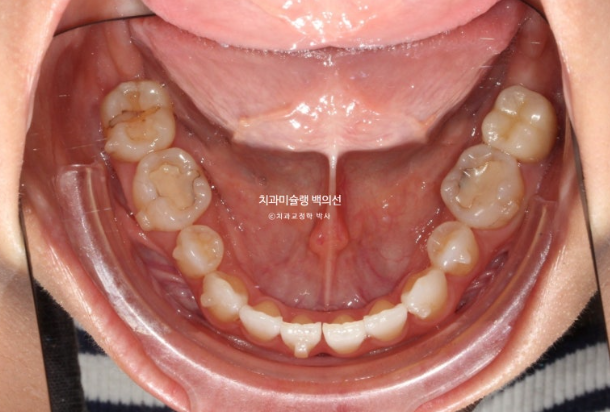

25년 7월부터 9월까지 7개 추가장치를 낀 후 치료를 마무리 했습니다.

25.09

총 치료기간은 6개월이고 재제작은 1회 했습니다.

철사 교정식 유지장치까지 꼼꼼하게 들어갑니다.